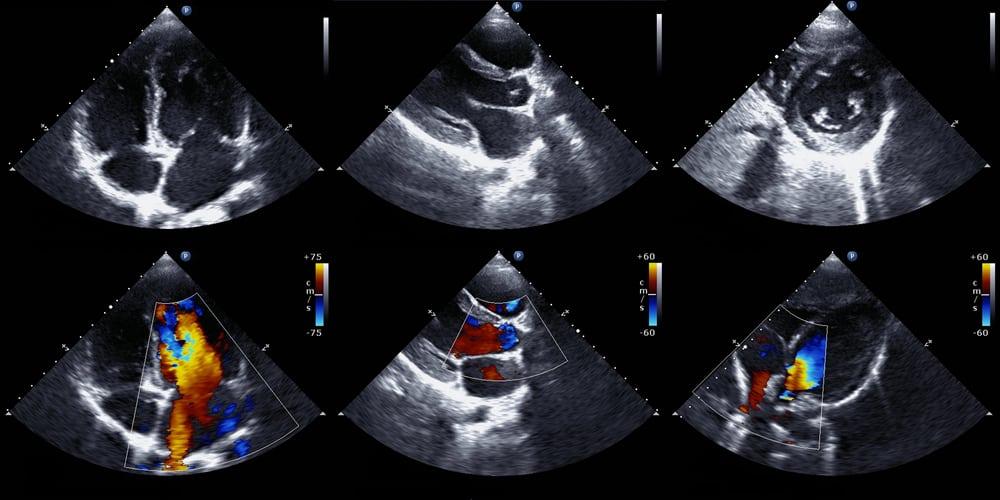

Siêu âm tim Doppler

Siêu âm tim Doppler thực chất là kết hợp thêm kỹ thuật Doppler với siêu âm 2D thông thường trong siêu âm tim qua lồng ngực và qua thực quản. Kỹ thuật Doppler được sử dụng để đo và đánh giá lưu lượng máu chảy qua các buồng tim và van tim cũng như trong lòng các mạch máu lớn ra vào tim. Lượng máu được bơm ra theo từng nhịp đập là một dấu hiệu cho thấy hoạt động của tim có bình thường hay không. Ngoài ra, kỹ thuật Doppler cũng giúp phát hiện vận tốc máu bất thường trong tim, các vấn đề với van tim và áp lực máu trong các động mạch liên quan. Theo đó, đây là các đặc điểm mà siêu âm tim thông thường không khảo sát được.